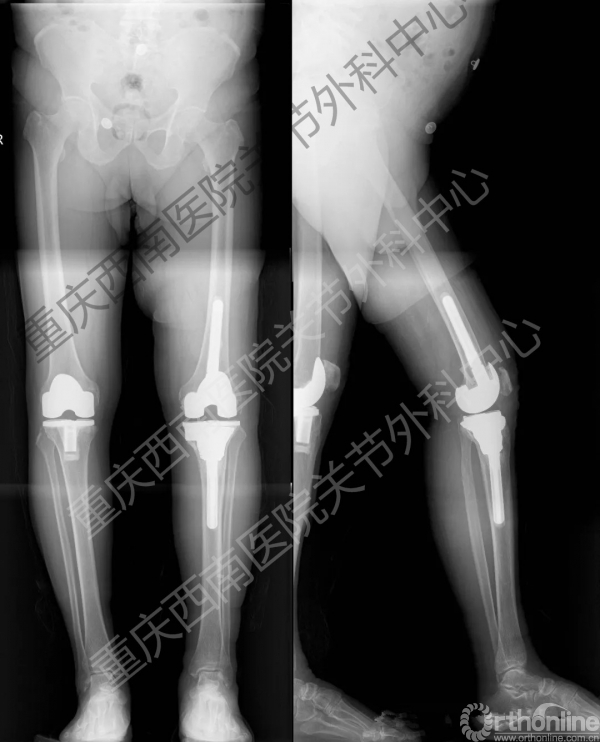

全膝关节翻修术后